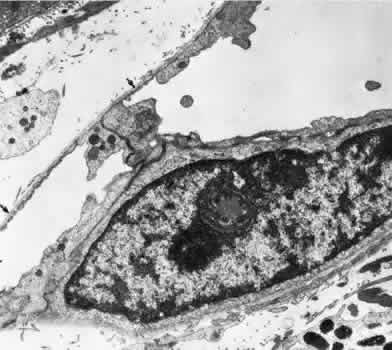

Retinal Veins and Venules Retinal veins are present in the inner retina, where they occasionally interdigitate with their associated arteries. When the two vessels cross, the artery usually lies anterior (toward the vitreous) to the vein.16 About one third of the time, however, the vein is anterior. At such crossing sites, the two vessels share a common adventitial coat.17 Under normal circumstances, the crossing vein's lumen may be decreased by as much as one third as a result of compression from the accompanying artery.17 There are many more arteriovenous crossings temporally than nasally, because the nasal vessels assume a much straighter course. Arteriovenous crossings are important because they represent the most common site of branch retinal vein obstructions. The separation of the superior and inferior halves of the perfusion of the retina is mirrored in the venous drainage pattern as well. Rarely does a retinal vein cross the horizontal raphe under normal circumstances. The retinal veins drain into the CRV, which also acts as the major efferent channel for the vessels of the optic nerve. Near the disc, the retinal veins are approximately 150 μm in diameter. Throughout the retina, the veins and venules generally follow the course of the arteries and arterioles. The intima of the veins consists of a layer of endothelial cells surrounded by a basement membrane continuous with that of the innermost layer of smooth muscle cells of the media. The media of the largest veins in the posterior retina consists of several layers of longitudinally oriented smooth muscle cells. The adventitia makes up the greatest part of the vessel wall and consists of loosely arranged collagen fibers and adventitial cells and is in direct contact with the glial cells of the retina. Venules are usually less than 20 μm in diameter.15 The media is composed of a single layer of cells resembling pericytes, containing poorly developed myofilaments and dense bodies. Elastin is not present. The adventitia contains little other than the basement membrane surrounding the pericyte (Fig. 5). Retinal Capillaries Throughout most of the posterior retina, the retinal capillaries are arranged anatomically in a dual layer. The superficial capillary layer is associated with the ganglion cell layer, whereas the deep capillary layer resides within the inner nuclear layer. Like capillary networks elsewhere in the body, the retinal capillaries assume a meshwork configuration to ensure adequate perfusion to all retinal cells. The deeper layer has a mesh diameter (i.e., the distance betweencapillaries) that characteristically averages 50 μm in diameter but varies between 15 and 130 μm. The more superficial layer has a slightly larger meshwork, on average 65 μm in diameter (16 to 150 μm). In the midequatorial and anterior zones, where the retina is thinner, only one capillary layer is present. In the fovea and the far retinal periphery, retinal capillaries are absent. The precise anatomical localization of the superficial layer of retinal capillaries appears to depend on the thickness of the accompanying ganglion cell layer.18 In the foveola itself and in the immediate parafoveal retina that contains a ganglion cell layer less than 15 μm thick, there are no superficial capillaries. This area represents the foveal avascular zone. Pathologic conditions that feature retinal capillary dropout, such as diabetes mellitus and sickle cell disease, may show an enlargement of this foveal avascular zone. Near the foveal margin, where the ganglion cell layer is of moderate thickness, the superficial retinal capillaries can be found in the outer aspect of the ganglion cell layer. In the intermediate parafoveal area, which has a ganglion cell region thicker than 45 μm, the superficial retinal capillaries are present within the ganglion cell layer itself. In the perifoveal region, where the ganglion cell layer is two to four cells thick, the superficial capillaries are found along the inner boundary of the ganglion cell layer, in contact with the nerve fiber layer. The major retinal vessels, especially the larger ones, usually are in contact with both the inner and outer boundaries of the ganglion cell layer. A capillary-free zone is present around each of the larger retinal arteries and veins (Fig. 6). It is more prominent around the arteries, measuring up to 100 μm. The capillary-free zone is a product of the embryologic vascular remodeling process. Direct diffusion of oxygen through the walls of the large retinal vessels probably initiates this process of vascular remodeling. Embryologically, numerous capillary-sized channels retract from the developing artery, leaving only a relatively few right-angled side-arm channels to serve as precapillary arterioles. In keeping these side channels to a minimum, the maintenance of an adequate pressure head for the remainder of the retina is ensured. In contrast, the radial peripapillary capillaries (RPCs) may develop in a different fashion, later than the other capillary beds, after vascular remodeling has already occurred.19 A distinct layer of capillaries, the RPC, is found adjacent to the optic disc, most prominently in the superior and inferior temporal aspects of the posterior pole (Fig. 7).20 These capillaries originate only from intraretinal arterioles and not from the optic disc vasculature. They are found within the inner aspect of the nerve fiber layer, making them the most superficial of all retinal capillaries. The RPCs tend to follow relatively long, straight paths, having few anastomoses with adjacent or underlying capillary beds. The RPCs do not traverse the central macular area. Their distribution suggests some anatomical correlation with various diseases. Cotton-wool spots are found in a distribution similar to the RPCs, and the arcuate scotoma seen in glaucoma appears to correspond to their pattern as well.21 The superficial peripapillary hemorrhages seen in glaucoma (Drance hemorrhages) may originate with the RPCs as well.22 Retinal capillaries range in diameter from 4 to6 μm. The capillaries throughout the retina, including those of the radial peripapillary network, have the same fine structure.23 The capillary wall consists of a continuous layer of flattened and longitudinally oriented endothelial cells and an incomplete layer of longitudinally oriented pericytes (Fig. 8). The pericytes (formerly referred to as mural cells) are closely spaced, resulting in an approximate ratio of pericytes to endothelial cells of 1:1, a relatively high ratio compared with elsewhere in the central nervous system. Ultrastructural examination of the endothelial cells of retinal capillaries shows that the cytoplasm of the cell bulges in the region of the nucleus. This area contains the Golgi apparatus, centrioles, and rough-surfaced endoplasmic reticulum. The remainder of the cytoplasm contains moderate amounts of smooth endoplasmic reticulum and mitochondria. The average endothelial cell thickness is 236 nm. Pinocytotic vesicles occur in the cells of the retinal capillaries. The vesicles are of uniform size, with an average diameter of 70 nm. Pinocytotic vesicles are found on the lumen (10% of total) and basement membrane (28%) side of the endothelial cells and free in the cytoplasm (62%). Approximately 2% of the volume of the endothelial cell is occupied by pinocytotic vesicles, a number that is substantially lower than that of other continuous capillaries. Pinocytotic vesicles of similar morphology and location are found in pericytes, but not in any number on glial cell membranes. Animal experimental evidence shows that these vesicles may be responsible for transporting substances from the vitreous cavity into the retinal vasculature in a unidirectional fashion.24 In the region of the endothelial cell junctions, cytoplasmic processes may overlap and form flap-like extensions that project into the lumen. The outer leaflets of adjacent endothelial membranes form very tight occluding junctions. The basement membrane surrounding the endothelial cell is well developed and continuous with the basement membrane surrounding the pericytes. The basement membrane of the retinal capillaries is structurally similar to that of the retinal arteries and veins in that collagen types 4 and 5, laminin, and heparin sulfate proteoglycan core protein are prominent features. Collagen types 1 and 2 appear to be lacking.12 Some areas show thinning of the basement membrane, and in these regions the endothelial cells and pericytes are closely apposed. Specifically, the capillary basement membrane between pericytes and endothelial cells is much thinner than the basement membrane covering the two types of cells.25 This arrangement probably allows increased communications between the cells. The retinal capillary basement membrane is thicker than in most other capillaries in the body, and in certain disease states such as diabetes, this thickness increases further.26 The pericytes of the retinal capillaries are not as elongated as the endothelial cells. They are endowed with multiple arm-like processes that wrap around the surrounding endothelial cells. Pericyte processes appear to cover about 85% of the entire circumference of the available capillary endothelial tube.25 Pinocytotic vesicles can be seen near the adventitial (outer) side of the cell body. In the peripheral retina, the retinal glial cells are in direct contact with the basement membrane surrounding the pericytes. Evidence suggests that the retinal pericytes are directly involved in the local control of retinal blood flow (RBF) and may affect endothelial proliferation as well.25 In diabetes there is an early, preferential loss of pericytes.27 Aldose reductase has been shown in the human pericyte, inviting speculation that abnormal accumulation of byproducts of this enzyme, such as polyol, may have a role in the selective pericyte loss.28 With aging there occurs a gradual loss of endothelial cells, followed by degeneration of the pericytes, an increase in capillary diameter, and a thickening and vacuolization of the capillary basement membrane surrounding the external surface of the pericyte.26,29 Age-related studies of larger retinal vessels show narrowing of the retinal arteries. This appears to be due to the fibrous replacement of contractile elements.17,30 These morphologic findings may account for the decrease in reactivity of the retinal arteries and arterioles to blood pressure and oxygen tension changes with age. A similar decrease in myogenic tone of the PCAs with age has also been demonstrated.31 OPTIC NERVE Most of the blood supply to the intraorbital portion of the optic nerve is through numerous perforating vessels from the pia mater. These pial vessels obtain their supply either directly from the ophthalmic artery or indirectly from recurrent branches back from the PCAs. There does not appear to be a “central artery of the optic nerve,” as once postulated.32,33 Axial branches off the CRA contribute to the circulation as well. The vascular supply of the optic nerve head was the source of considerable controversy in the past. The optic nerve head is situated at the watershed area between three separate circulations: the retinal, the posterior ciliary, and the pial (Fig. 9). Each of these systems contributes in part to the optic nerve head circulation. In some people, an incomplete arterial ring is formed within the sclera by the anastomoses of these three circulations. When present, it is referred to as the circle of Zinn-Haller. Most of the prelaminar blood flow is derived from the posterior ciliary circulation by way of the short PCAs.34,35 The prelaminar optic nerve may have separate tributaries from the short PCAs, or branches of these vessels may supply the optic nerve directly, as well as the choroid.36 There do not appear to be any direct anastomoses between the choriocapillaris and the capillaries of the optic nerve head, however. Neither are there major contributions from axial branches of the CRA. The circle of Zinn-Haller may contribute to the prelaminar circulation, but the pial arteries do not directly supply the prelaminar portion. They may anastomose with the prelaminar capillary network, however. The laminar portion of the optic nerve head is also supplied by the short PCAs, with variable contributions from the circle of Zinn-Haller.37 The CRA does not appear to contribute much to the supply of this area (Figs. 9 and 10).